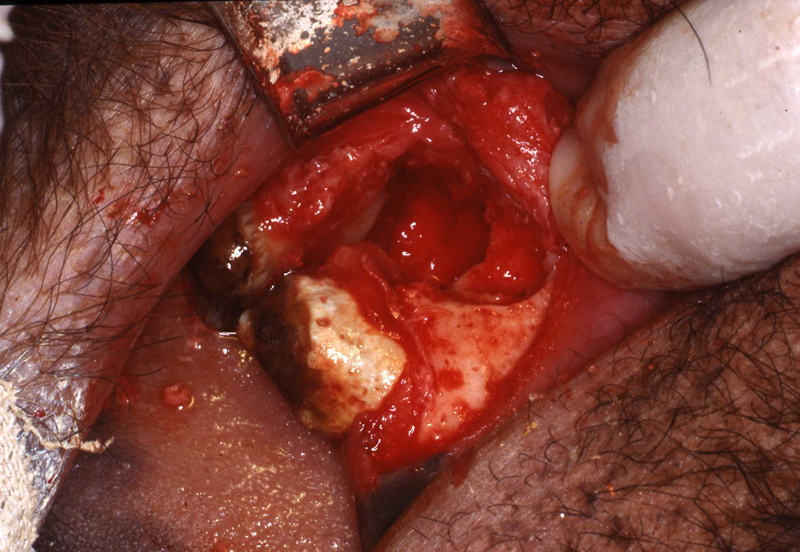

Fistula explored

Fistula exposed

Fistula being repaired

Fistula exposed, tensionless flap